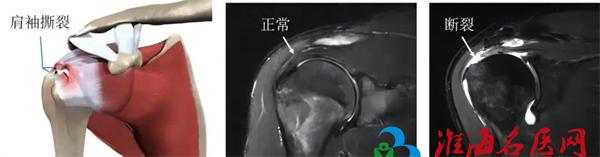

什么是肩袖损伤?

肩袖是包围我们肩关节的一组重要肌腱群,它们像“袖子”一样紧紧包裹着肩关节,负责肩关节的旋转、上举等各个方向的运动。由于退变、外伤或过度使用,这些肌腱可能发生撕裂,导致疼痛、无力、活动受限,这就是肩袖损伤。肩袖损伤不仅影响日常生活,还可能对工作造成严重影响。